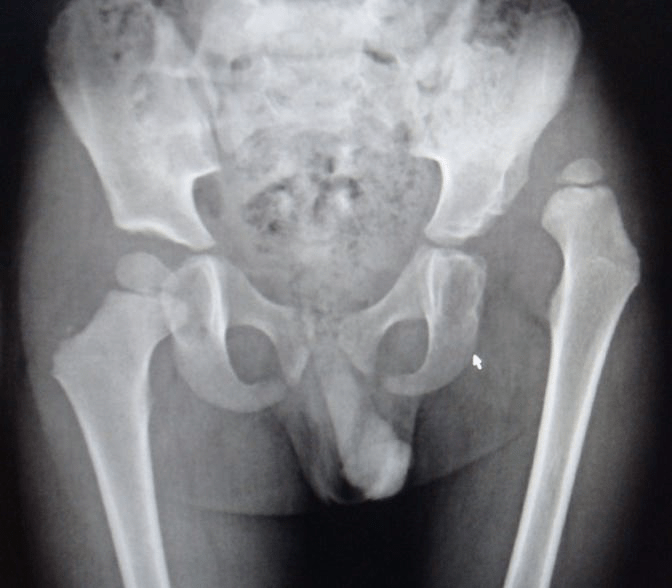

3+5 year old Pre and post-op (Adductor tenotomy hip, OR, Femoral & Pelvic Osteotomy with spica)